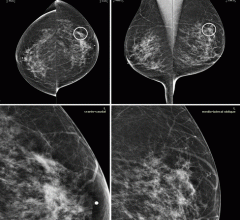

Mammography is a breast imaging technique that uses X-rays to diagnose and locate tumors of the breasts.

November 11, 2020 — Digital breast tomosynthesis (DBT), in combination with synthetic mammography, improves cancer ...